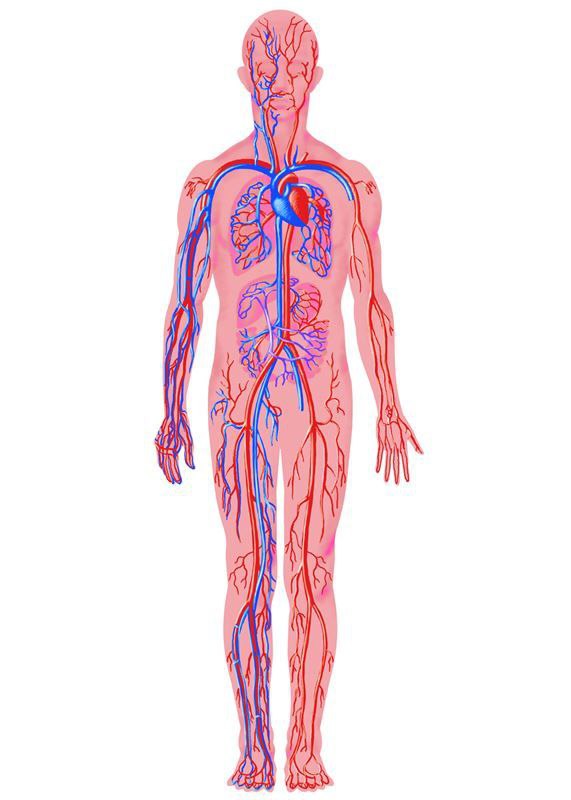

Анатомия человека: кровеносная система и её связь со скелетом